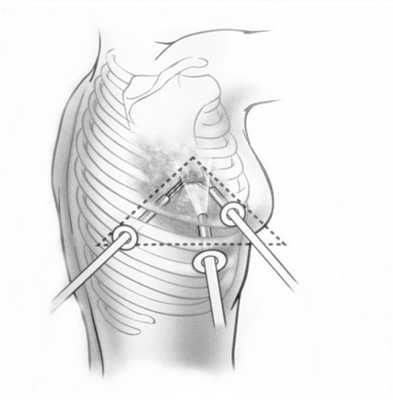

При лечении местнораспространенного злокачественного образования с переходом на главный бронх и лёгочную артерию, в тех случаях, где раньше единственным вариантом оперативного лечения являлась пневмонэктомия, сейчас возможно выполнение органосохранных операций. В этом случае иссекается пораженный участок главного бронха с последующим восстановлением непрерывности (бронхопластические и ангиопластические лобэктомии)

Фото 5 — Схема верхней бронхопластической лобэктомии